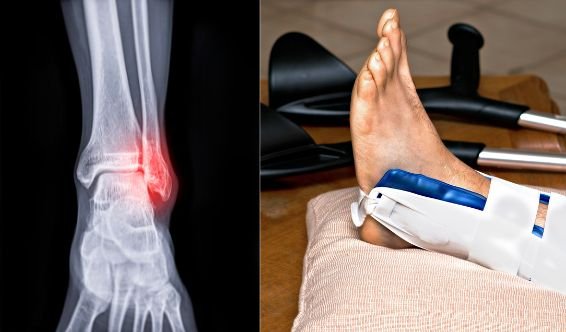

Fracture cheville / pied

Très fréquent : œdème, raideur et instabilité. Objectif : mobilité, proprioception, marche stable, prévention des entorses/chutes.

Rééducation après fracture de cheville à domicile au Maroc

Fracture de cheville : mobilité, stabilité, proprioception et marche sans boiterie.

Fracture de cheville : pourquoi la proprioception est indispensable ?

Après une fracture de cheville, l'articulation peut être raide, mais surtout elle peut perdre sa capacité à "sentir" l'appui et à se stabiliser. La proprioception réentraîne l'équilibre, le contrôle des appuis et la réaction aux petits déséquilibres du quotidien. Sans ce travail, on garde souvent une sensation d'instabilité, une boiterie, ou une peur de poser le pied normalement. C'est justement ce qui aide à reprendre une marche plus fluide et à réduire les rechutes et entorses secondaires.